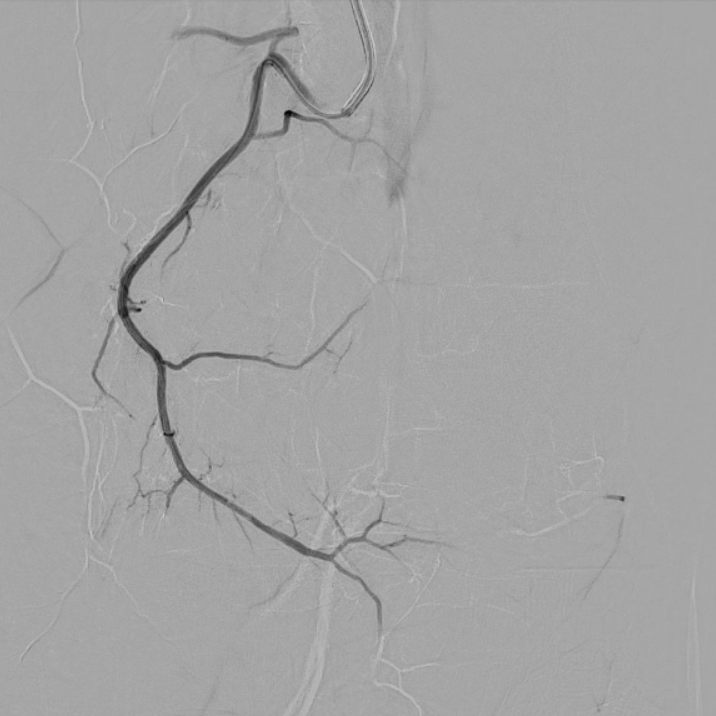

case of the day - 10.02.2026

Kniegelenk

Hier sehen Sie die Behandlung des medialen Kniegelenks. Mithilfe des "Okklusionstricks" konnte man das Embolisat mit Druck über die Kollateralen bis zur A. genicularis inferior lateralis bringen.

Arteria genicularis superior medialis - vor Behandlung

Arteria genicularis superior medialis - nach Behandlung